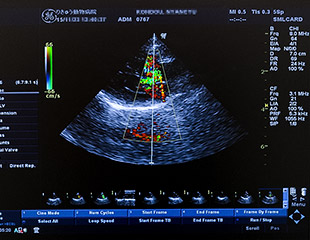

腹部超音波検査、心臓超音波検査

超音波検査では、レントゲン検査が苦手としている、臓器内部の詳細構造の確認がリアルタイムで可能です。

一方で、超音波検査というものは、臓器のある一部分だけを覗いているようなかたちですので、レントゲン検査が得意とする、臓器の全体像(大きさ・形)や位置関係の把握についてはやや苦手としています。また、空気を含む臓器(肺・ガスが多い消化管)や骨そのもの、または骨で囲まれた臓器も苦手としています。超音波検査はレントゲン検査と組み合わせることで素晴らしいパフォーマンスを発揮する検査です。

超音波検査では、臓器の炎症像や内部構造の異常、レントゲン検査では検出できないような腫瘤の有無などを確認できるほか、リアルタイムの検査となりますので、臓器の動きについても確認できます。

当院が導入している超音波診断装置にはカラードップラーモードというものがあり、血流の向きや速度が検出できます。このパフォーマンスが最も発揮されるのが心臓です。心臓病に罹患すると、心臓の構造が異常になったり、血液が逆流したりするほか、ステージに伴って、血流速に変化が認められるなどします。心臓病のステージ把握には、必須の検査となります。

検査は診断する臓器の種類にもよりますが、数分から10数分かかります。人手が必要となるので、混雑状況によっては、一時的に動物をお預かりする場合がございます。